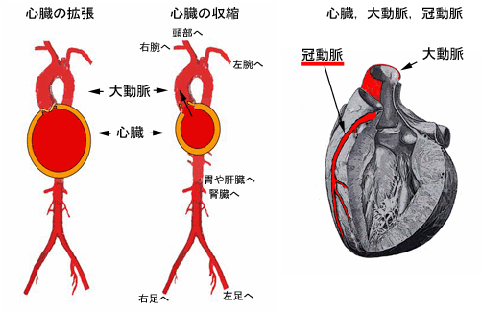

血管年齢・頸部エコー・動脈硬化について | 名古屋市昭和区 横山, ストップ!動脈硬化「危険を予測 最新検査」 - きょうの健康 - NHK,

ストップ!動脈硬化「危険を予測 最新検査」 - きょうの健康 - NHK, 循環器検査 | 名古屋循環器科・内科 | 中村区名駅,

四谷三丁目・四谷・四ツ谷の内科・循環器内科・外科 | まがり, 心臓・血管の専門検査 - 名古屋市名東区 内科 循環器内科 皮膚科,

心臓・血管の専門検査 - 名古屋市名東区 内科 循環器内科 皮膚科, 血管エコーの最新動向 - 新。超音波診断 Vol.03 - 東芝,

血管エコーの最新動向 - 新。超音波診断 Vol.03 - 東芝, シャント血管治療(VAIVT)センター|医療法人相生会|西片貝